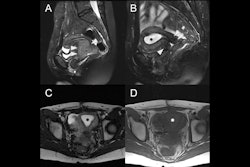

MRI is used as the second-line modality when ultrasound cannot provide conclusive answers. "This may occur in selective cases when doubts exist regarding the benign/malignant nature of the supposed fibroid, or when MRI is necessary to assess eligibility for minimally invasive (uterine artery embolization) and non-invasive (MR-guided high-intensity focused ultrasound) treatments.”

Tomographic 2D and 3D MRI may also provide critical information, with more anatomical details and better soft-tissue contrast, they added.